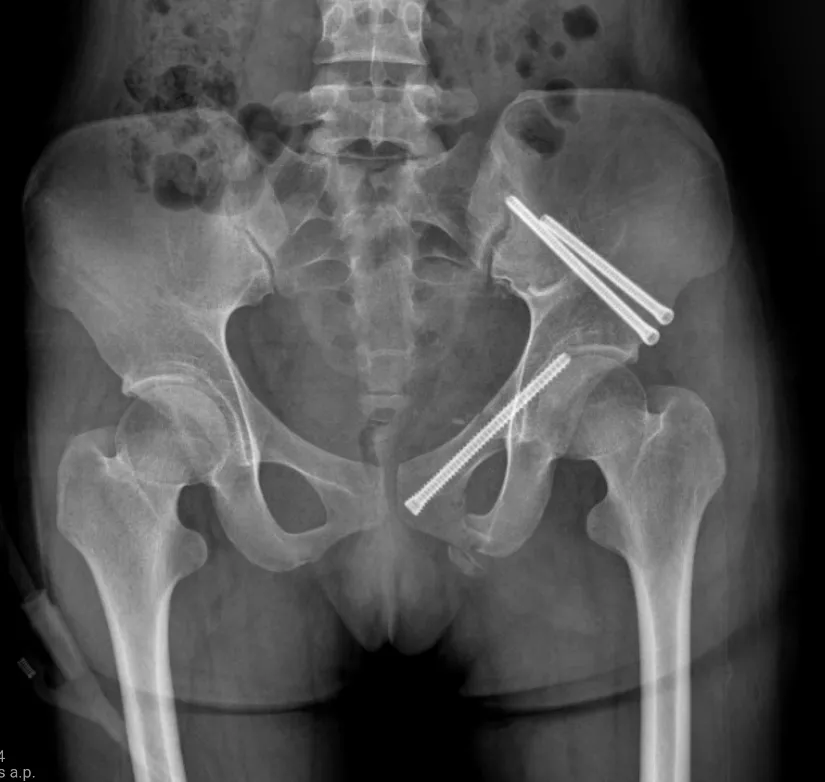

術后X光片(下)

針對小陳這樣的案例,使用的經皮恥骨支螺釘內固定術是一種髓內固定技術,在治療骨盆前環損傷中得到了越來越廣泛的應用,常用于恥骨上支骨折和髖臼前柱骨折。經過實踐分析,這是治療單側恥骨骨折的最佳治療方式,具有手術創傷小、術中出血量少、固定強度大、并發癥少及功能恢復快等優點。